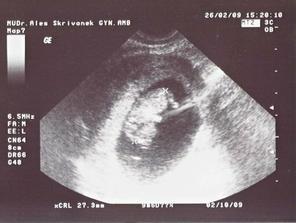

26/2 09 PORADNA 10 + 4 tt - přítel je semnou 🙂) - ta naše "žížalka" je líná a otočená zadečkem k nám, až když mi dr. začne mačkat břicho tak se otočí a ukáže ručičky a nožičky, měříme 2,7 cm, máme první fotku